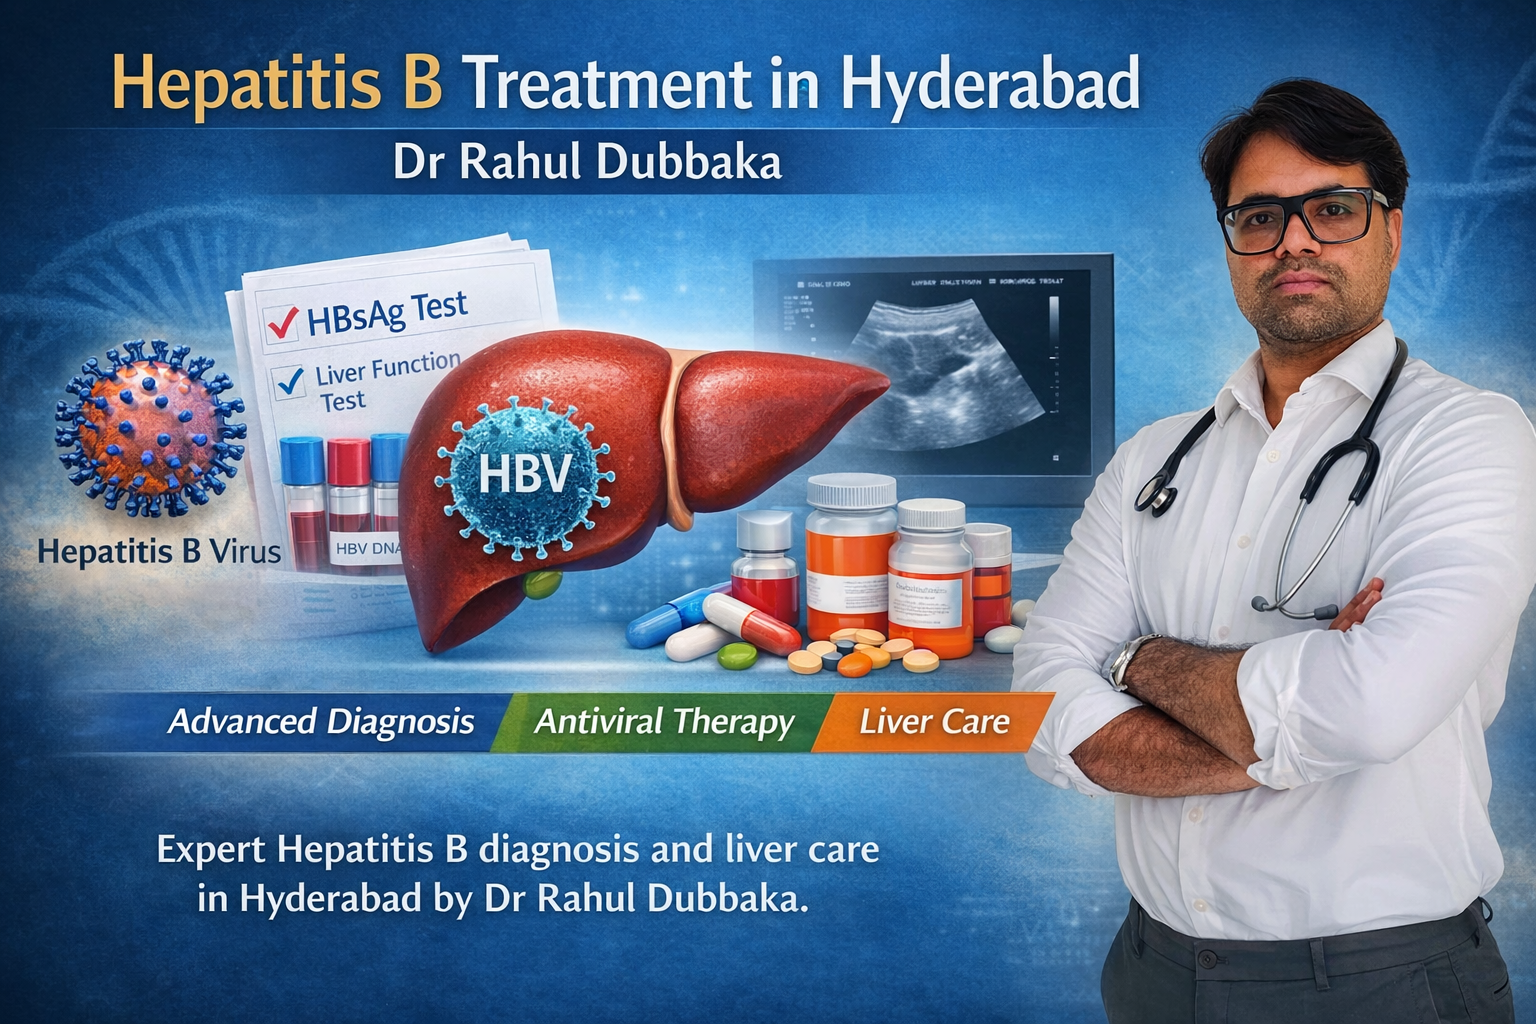

Hepatitis C Treatment in Hyderabad – Expert Care

Looking for Hepatitis C treatment in Hyderabad? Dr Rahul Dubbaka offers advanced antiviral therapy with 95%+ cure rates at People’s Hospital, Pragathi Nagar. Book your consultation today at +91 9100921514. Hepatitis C is a viral infection that primarily affects the liver and can silently damage it over time. If left untreated, it may lead to serious complications such as cirrhosis, liver failure, and even liver cancer. The good news is that with modern medical advancements, Hepatitis C is now highly curable with effective antiviral medications.

If you are searching for Hepatitis C Treatment in Hyderabad, consulting an experienced gastroenterologist and hepatologist like Dr Rahul Dubbaka can ensure accurate diagnosis, personalized treatment, and long-term liver health management.

Dr Rahul Dubbaka practices at People’s Hospital, offering advanced liver care services for patients across Hyderabad.

Why Choose Dr Rahul Dubbaka for Hepatitis C Treatment in Hyderabad?

Dr Rahul Dubbaka is a reputed gastroenterologist and liver specialist with expertise in managing chronic liver diseases.

Diagnosis of Hepatitis C

Accurate diagnosis is essential before starting treatment.

1. HCV Antibody Test

Detects exposure to the virus.

2. HCV RNA PCR Test

Confirms active infection and measures viral load.

3. Liver Function Tests (LFTs)

Assess liver inflammation and damage.

Modern Treatment Options for Hepatitis C

The introduction of Direct-Acting Antivirals (DAAs) has revolutionized Hepatitis C treatment.

Book Your Hepatitis C Consultation Today

If you or a loved one has been diagnosed with Hepatitis C, consult Dr Rahul Dubbaka at People’s Hospital for expert evaluation and advanced treatment.